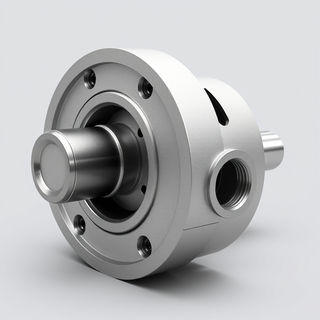

Simplify medical equipment specs for everyone.Open# Infusion Pump An infusion pump is a medical device used to deliver fluids, medications, or nutrients into a patient's body in controlled amounts. ## Purpose - Administer intravenous (IV) fluids, medications, blood products, and nutritional supplements - Provide precise control over delivery rates and volumes - Allow for continuous or intermittent administration ## Types 1. **Volumetric pumps**: Deliver larger volumes of fluids 2. **Syringe pumps**: For smaller volumes and more precise control 3. **Patient-controlled analgesia (PCA) pumps**: Allow patients to self-administer pain medication 4. **Ambulatory pumps**: Portable devices for mobile patients 5. **Enteral pumps**: For delivering nutrition directly to the gastrointestinal tract ## Key Features - Programmable delivery rates and volumes - Multiple delivery modes (continuous, intermittent, bolus) - Alarm systems for occlusions, air-in-line, low battery, etc. - Drug libraries with pre-programmed safety limits - Data logging and connectivity with electronic health records ## Safety Considerations - Proper programming to avoid over- or under-infusion - Regular maintenance and calibration - Battery backup systems - Infection control protocols for IV line management - Staff training on proper use and troubleshooting ## Common Procedures - IV fluid administration - Chemotherapy delivery - Antibiotic therapy - Pain management - Parenteral nutrition ## Usage Instructions 1. Verify patient identity and prescribed therapy 2. Prime tubing and connect to patient's IV access 3. Program pump with correct medication, dose, and rate 4. Start infusion and monitor regularly 5. Respond promptly to any alarms 6. Document administration in patient records

Simplify medical equipment specs for everyone.Open# Infusion Pump An infusion pump is a medical device used to deliver fluids, medications, or nutrients into a patient's body in controlled amounts. ## Purpose - Administer intravenous (IV) fluids, medications, blood products, and nutritional supplements - Provide precise control over delivery rates and volumes - Allow for continuous or intermittent administration ## Types 1. **Volumetric pumps**: Deliver larger volumes of fluids 2. **Syringe pumps**: For smaller volumes and more precise control 3. **Patient-controlled analgesia (PCA) pumps**: Allow patients to self-administer pain medication 4. **Ambulatory pumps**: Portable devices for mobile patients 5. **Enteral pumps**: For delivering nutrition directly to the gastrointestinal tract ## Key Features - Programmable delivery rates and volumes - Multiple delivery modes (continuous, intermittent, bolus) - Alarm systems for occlusions, air-in-line, low battery, etc. - Drug libraries with pre-programmed safety limits - Data logging and connectivity with electronic health records ## Safety Considerations - Proper programming to avoid over- or under-infusion - Regular maintenance and calibration - Battery backup systems - Infection control protocols for IV line management - Staff training on proper use and troubleshooting ## Common Procedures - IV fluid administration - Chemotherapy delivery - Antibiotic therapy - Pain management - Parenteral nutrition ## Usage Instructions 1. Verify patient identity and prescribed therapy 2. Prime tubing and connect to patient's IV access 3. Program pump with correct medication, dose, and rate 4. Start infusion and monitor regularly 5. Respond promptly to any alarms 6. Document administration in patient records -